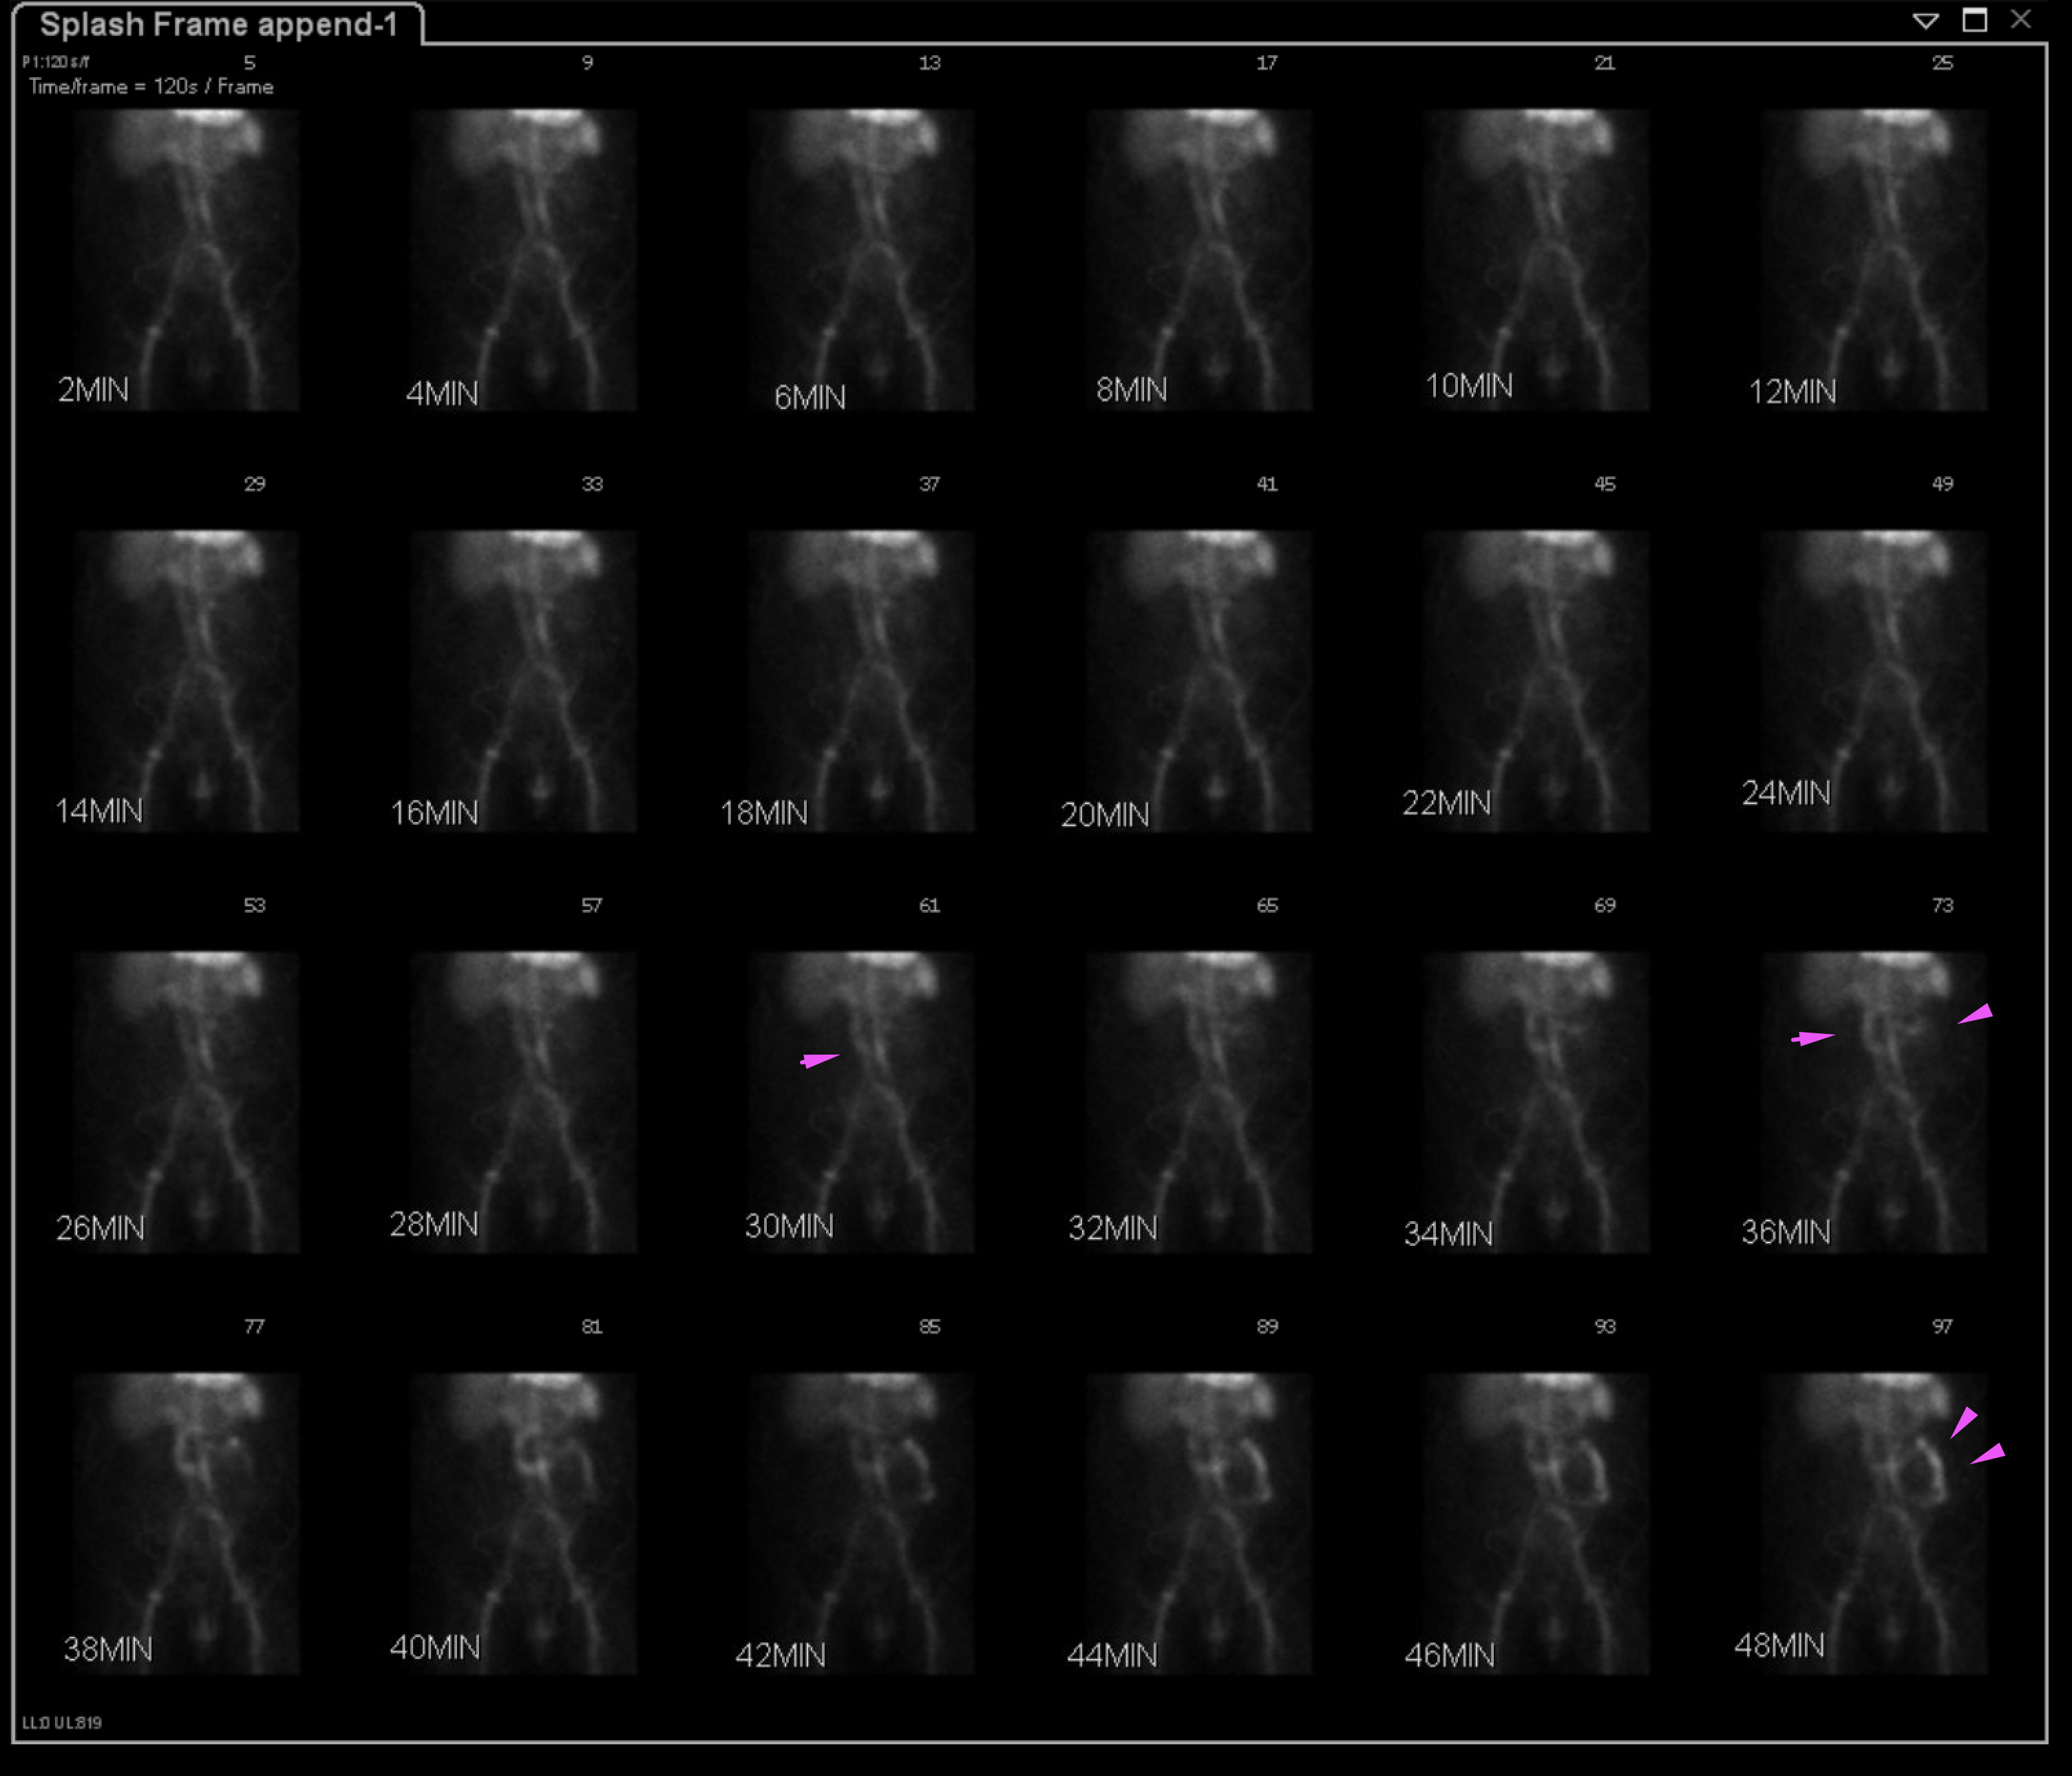

Age: 72

Sex: Male

Indication: GI bleeding

Radiotracer: Tc99m labeled RBCs

Sample ReportEvidence of active GI bleeding during the course of this study with likely source in the proximal duodenum.